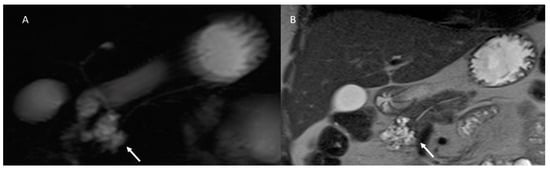

- Hecht, E.M.; Khatri, G.; Morgan, D.; Kang, S.; Bhosale, P.R.; Francis, I.R.; Gandhi, N.S.; Hough, D.M.; Huang, C.; Luk, L.; et al. Intraductal papillary mucinous neoplasm (IPMN) of the pancreas: Recommendations for Standardized Imaging and Reporting from the Society of Abdom.inal Radiology IPMN disease focused panel. Abdom. Radiol. 2020, 46, 1586–1606. [Google Scholar] [CrossRef] [PubMed]

- Waters, J.A.; Schmidt, C.M.; Pinchot, J.W.; White, P.B.; Cummings, O.W.; Pitt, H.A.; Sandrasegaran, K.; Akisik, F.; Howard, T.J.; Nakeeb, A.; et al. CT vs. MRCP: Optimal Classification of IPMN Type and Extent. J. Gastrointest. Surg. 2007, 12, 101–109. [Google Scholar] [CrossRef]

- Pilleul, F.; Rochette, A.; Partensky, C.; Scoazec, J.-Y.; Bernard, P.; Valette, P.-J. Preoperative evaluation of intraductal papillary mucinous tumors performed by pancreatic magnetic resonance imaging and correlated with surgical and histopathologic findings. J. Magn. Reson. Imaging 2005, 21, 237–244. [Google Scholar] [CrossRef]